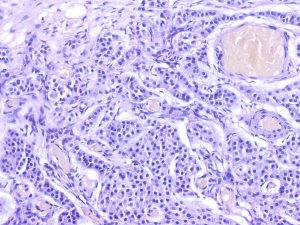

Rete Testis-Associated Nodular Steroid Cell Nests (RTANSCN) – unencapsulated nodules measuring less than 3 mm, located in rete testis. RTANSCN are composed of eosinophilic cells with round nuclei and variable prominent nucleoli arranged in nests and trabeculae with sticking sinusoidal vasculature and retraction artefact. Intracytoplasmatic Reinke crystals or lipochrome pigment are not present.

Immunohistochemical examination shows variable inhibin and calretinin expression, and strong Melan A immunostaining.